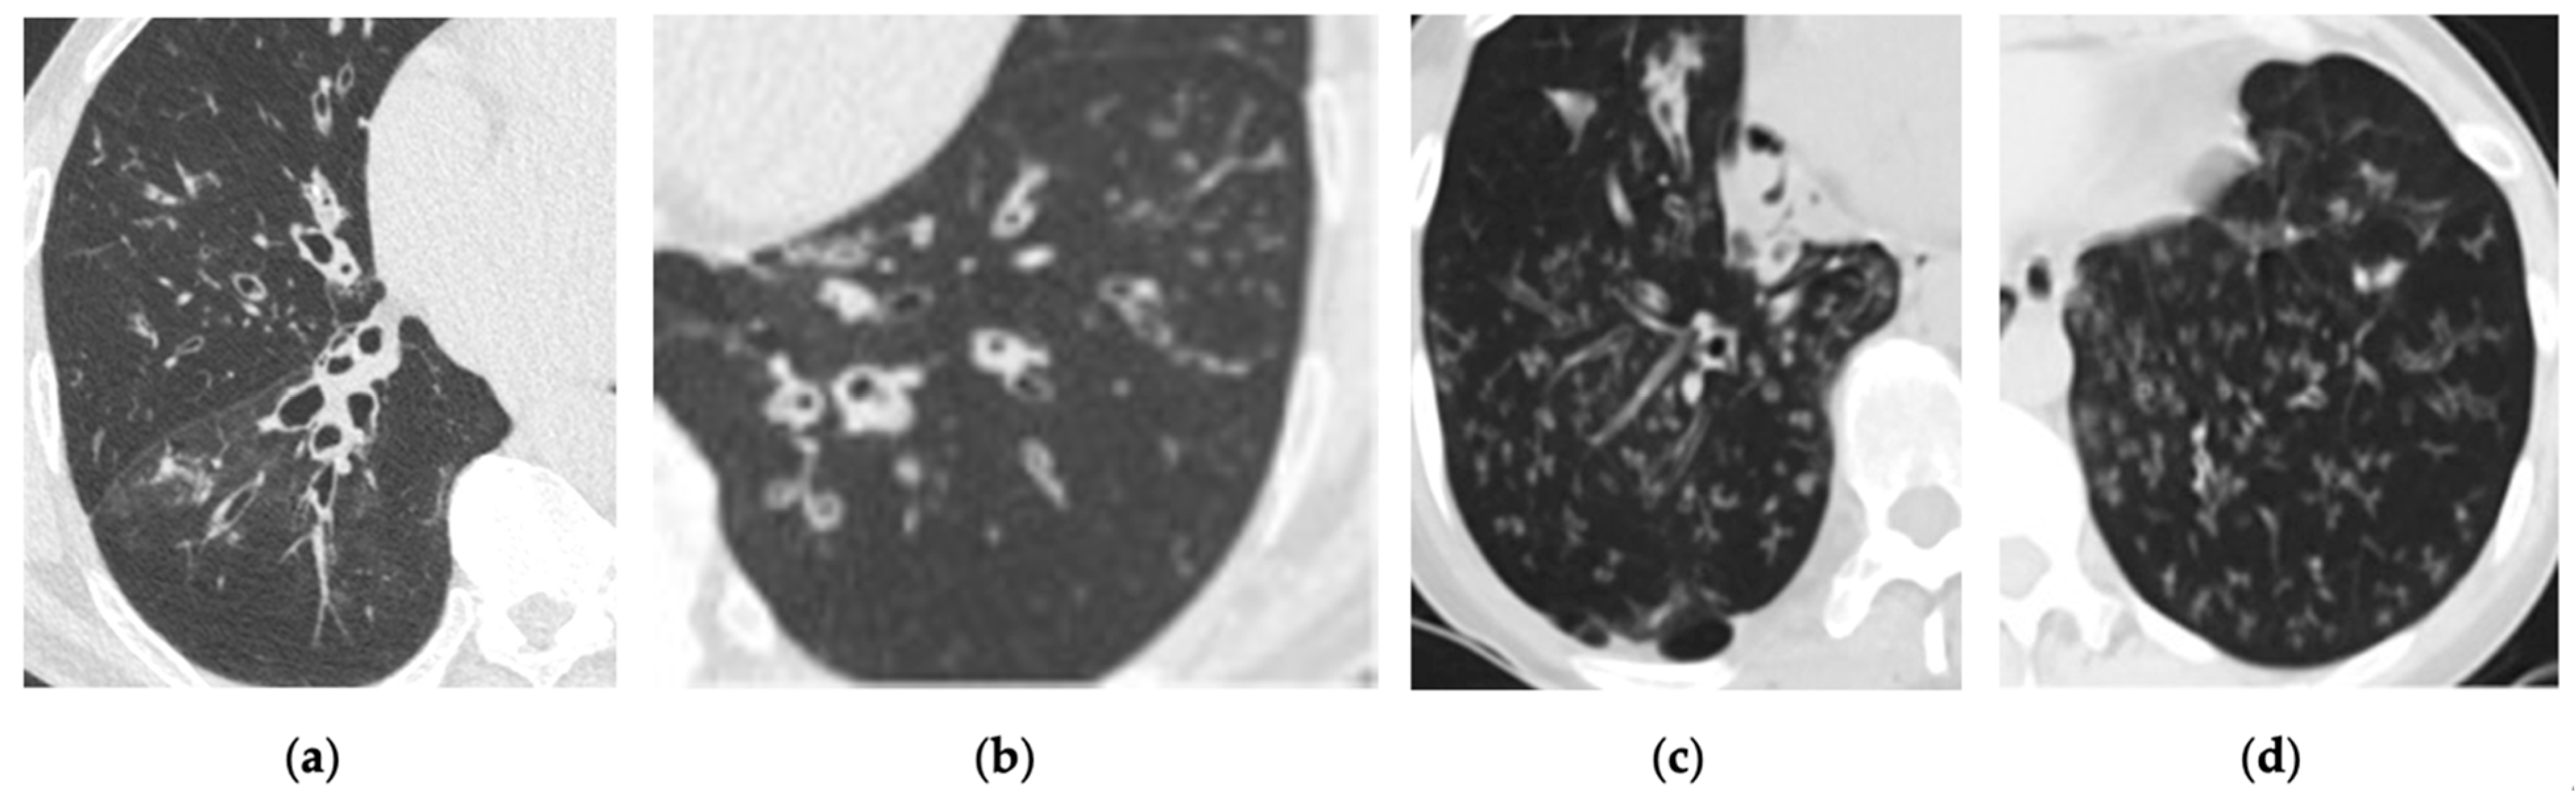

3.2. Interstitial Lung Diseases (ILDs)